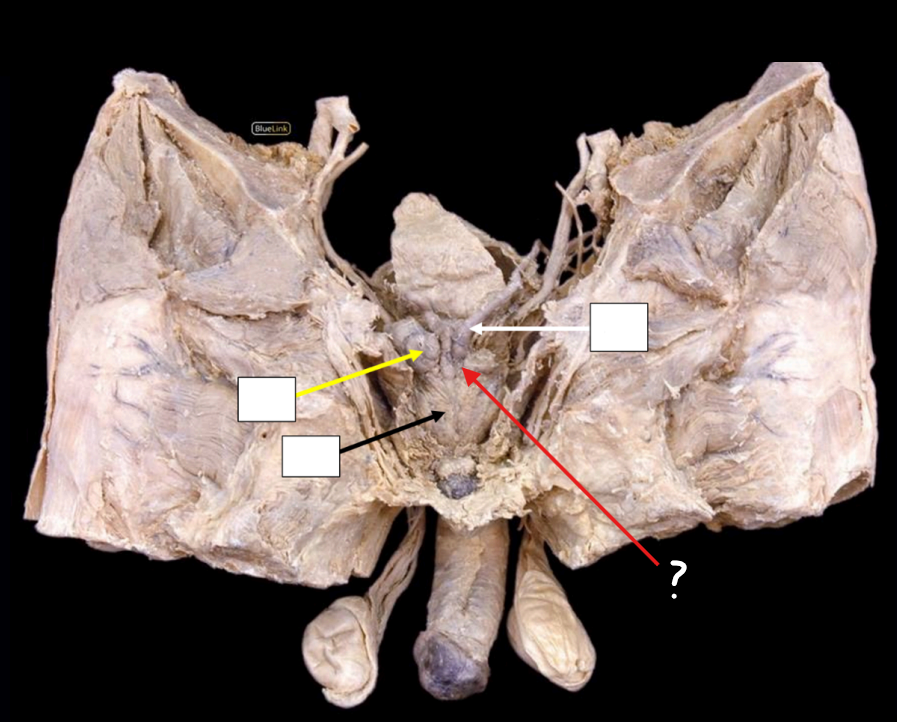

Identify #1

Side Questions:

Blood Supply?

Origin

Nerve Supply?

Lymph Drainage?